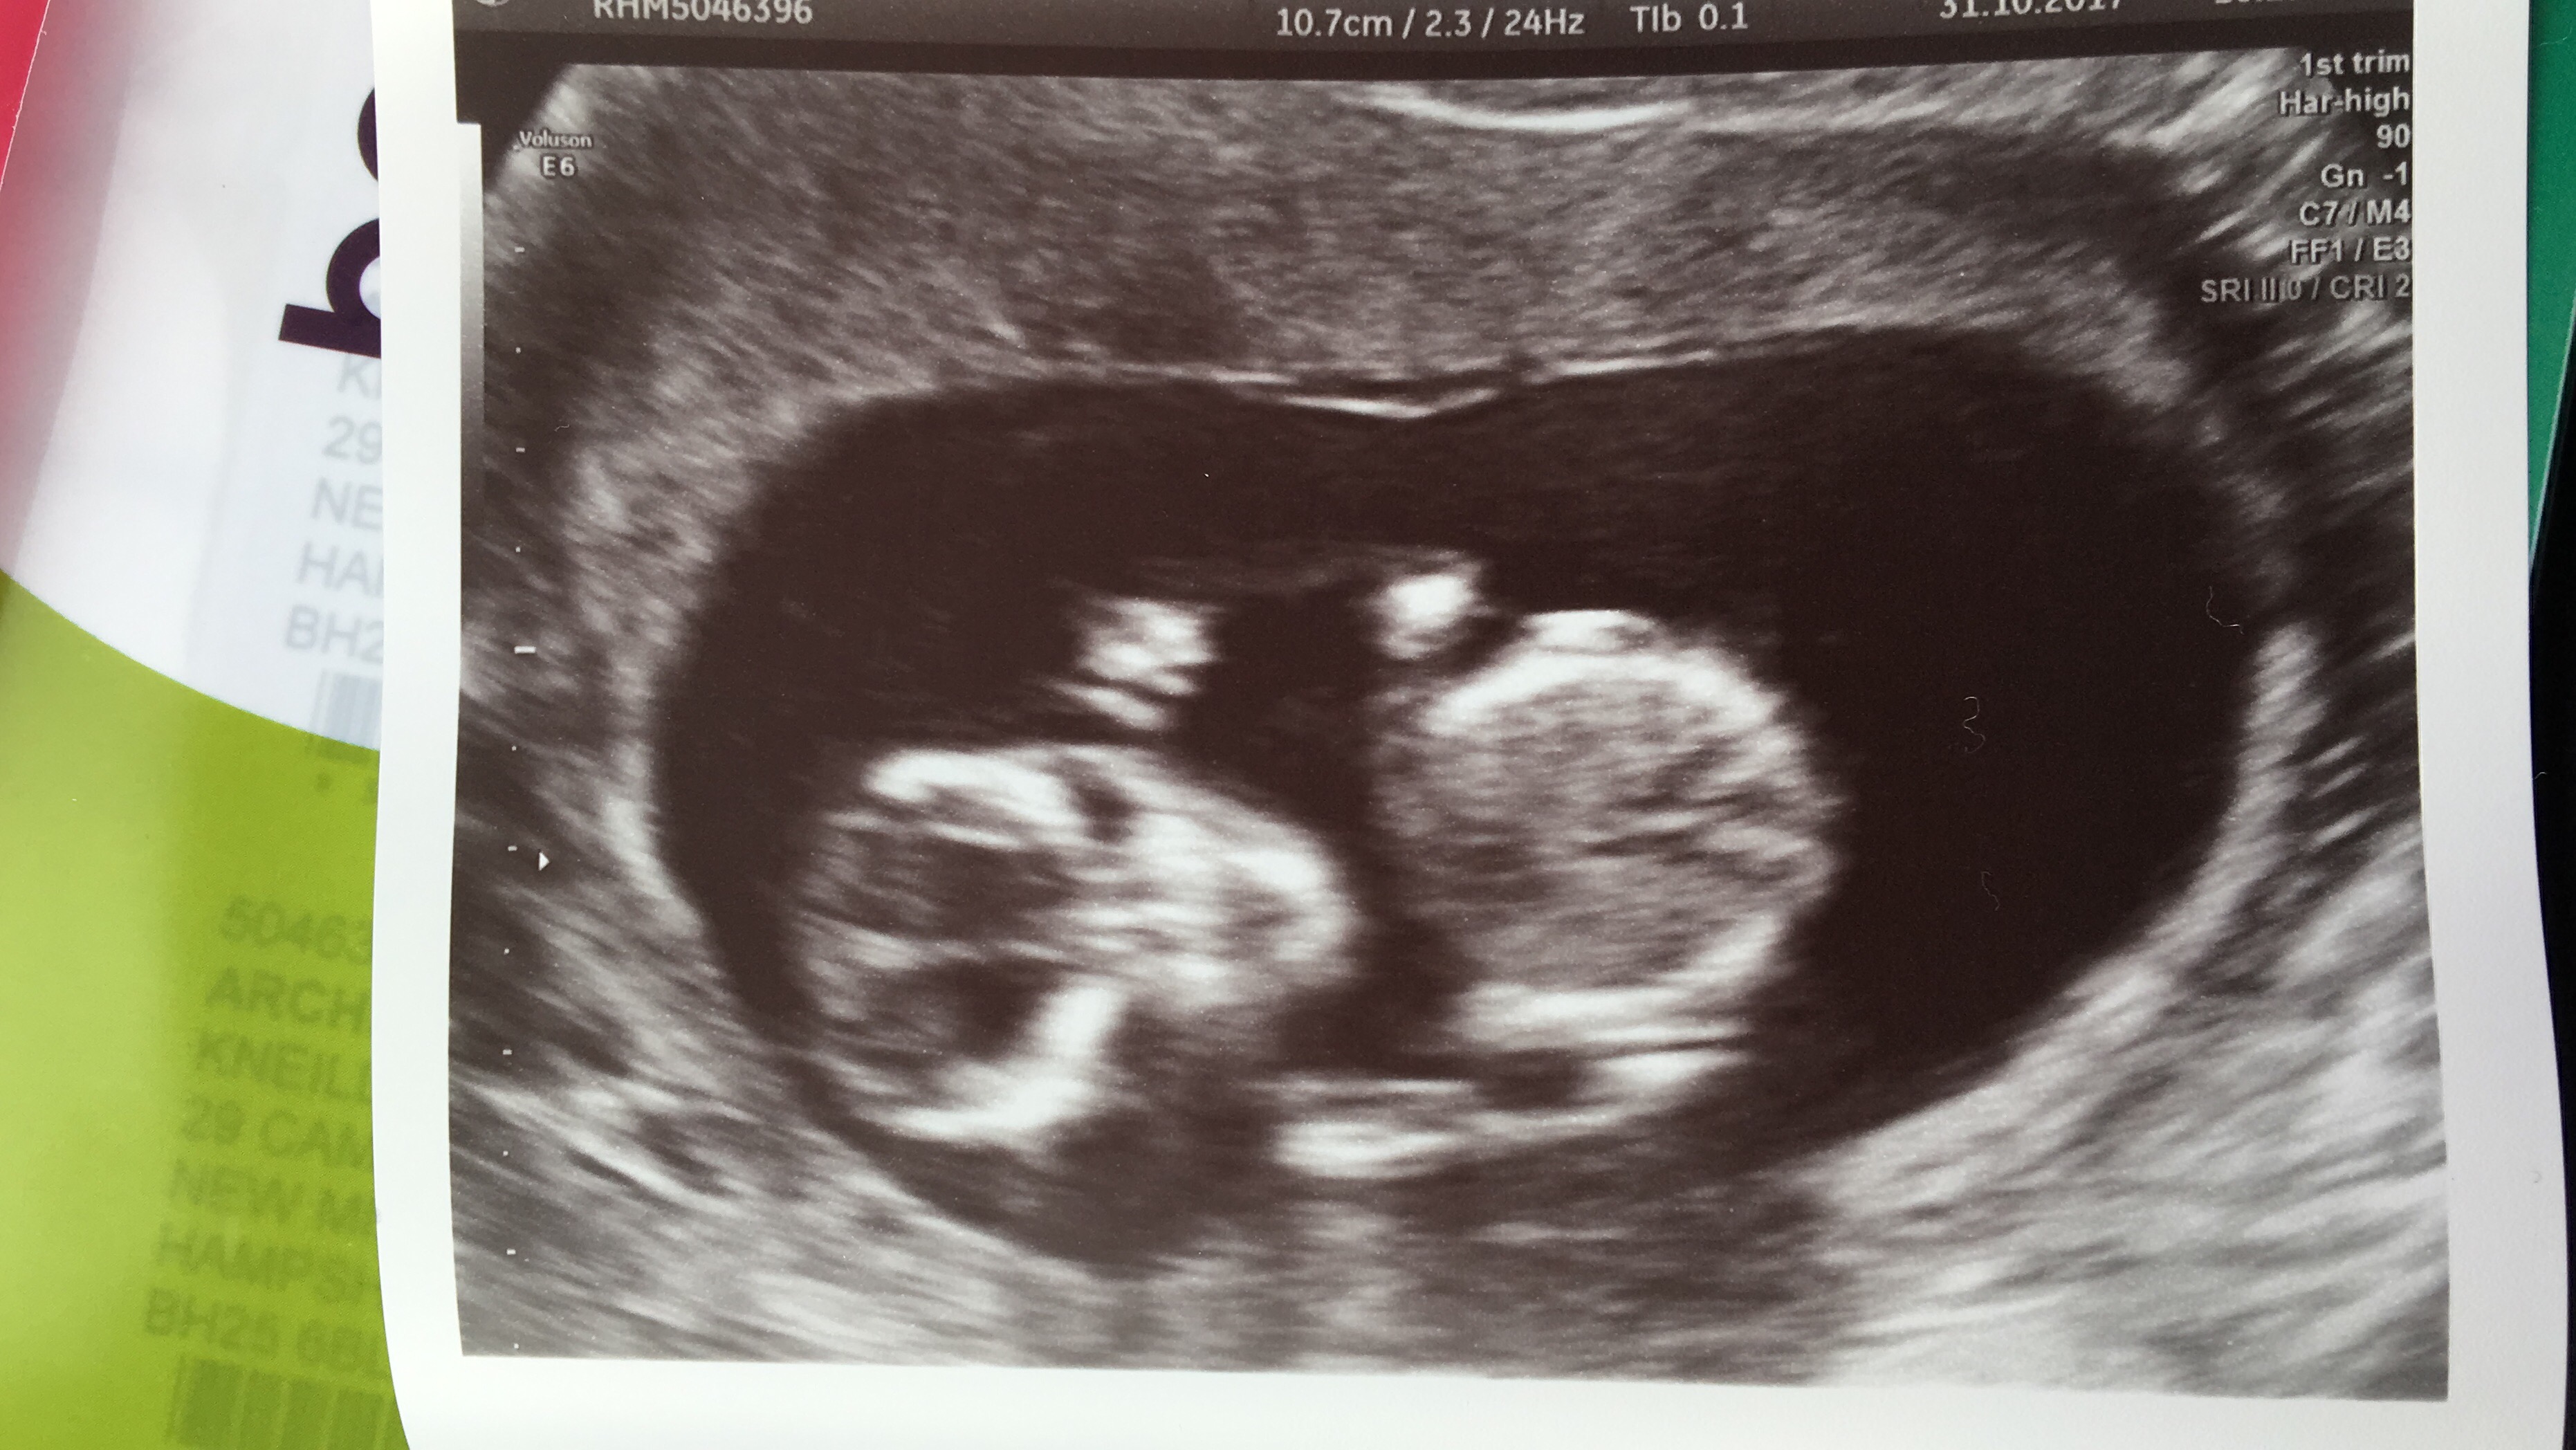

I’ve had both 12 week and 20 week scans and thought I wanted the surprise 3 rd time round but that’s proving more difficult as I approach my 4d scan in Feb. I already have 2 DS and would dearly love a little pink one to complete me but this baby is the last so either way I’m done as financially, spacially and practically we can’t afford anymore.I have thought girl from day one of conception for numerous reasons, timed conception (5-8dpo), feeling very nauseous, strong metallic taste in my mouth which is still present, bad breakouts all of which I didnt have with my boys. I’d be very interested to know what you all think 🤔 Attachment 38554Attachment 38556